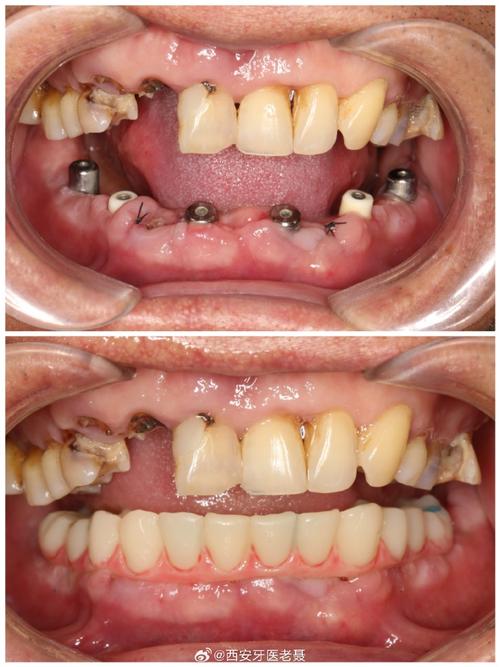

种植牙种太深的危害不容忽视,最直接的是对邻近解剖结构的损伤:当下颌后牙区种植体过深时,可能压迫或损伤下牙槽神经,导致下唇、颏部麻木、感觉异常,严重者可出现持续性疼痛;上颌后牙区种植体若穿透上颌窦黏膜,可能引发上颌窦炎,表现为鼻塞、流脓、面部胀痛,甚至导致种植体周围感染,种植体位置过深会影响修复效果:种植体平台低于牙槽嵴顶过多,会导致基台连接困难,修复体高度不足,影响咬合功能;牙龈组织因缺乏足够支撑可能出现萎缩,影响美观,远期来看,种植体过深还可能因周围血供差、应力集中等问题,增加种植体周围炎、骨吸收甚至种植体松动的风险。

针对种植牙种太深,处理方法需根据具体情况选择,若术中即时发现,且种植体位置偏差较小,可通过调整基台角度或使用个性化基台补救;若已侵入重要结构(如下颌管、上颌窦),需及时取出种植体,待骨愈合后重新植入,术后若出现神经损伤,可给予甲钴胺、维生素B族等营养神经药物,多数患者在3-6个月内可逐渐恢复;若合并上颌窦炎,需进行抗感染治疗,必要时行上颌窦修补术,对于修复期患者,可通过牙龈成形术、临时冠引导牙龈塑形等方式改善美观,若咬合问题严重,可能需拆除修复体重新制作。